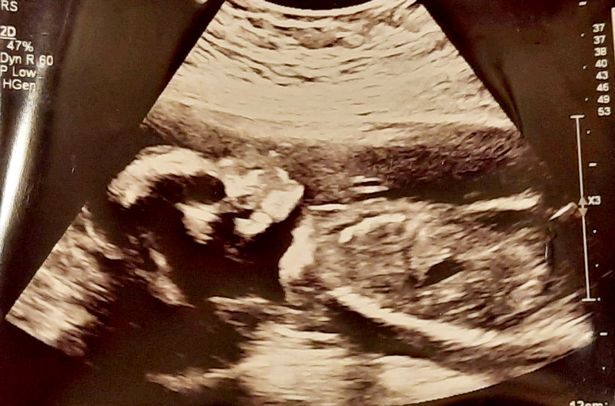

Uma mãe ficou extremamente assustada com a imagem de sua filha no ultrassom na Escócia. Com cinco meses de gravidez aproximadamente, Tasmin Stenhouse, de 25 anos, estava ansiosa para ver o rosto da primeira filha. No entanto, o que antes era empolgação se transformou em desespero quando visualizou uma imagem em preto e branco que mostrava uma “formação craniana diferente”, de acordo com o site de notícias britânico The Mirror.

O ultrassom mostrou o feto com uma aparência de caveira – Foto: Reprodução/Internet/NDO ultrassom mostrou o feto com uma aparência de caveira – Foto: Reprodução/Internet/ND

Inicialmente, o choque se deu por conta das características faciais que eram mostradas na imagem, que se assemelhavam a uma caveira. No entanto, em seguida, o pai da criança deu risada da situação e disse gargalhando que não parecia “tão assustadora”.

A mãe informou que com esse exame eles conseguiram descobrir o sexo da criança. Ela ainda completa que essa foi “uma das primeiras imagens claras que tivemos dela. Mostrei ao meu parceiro e sua reação foi cair na gargalhada”.